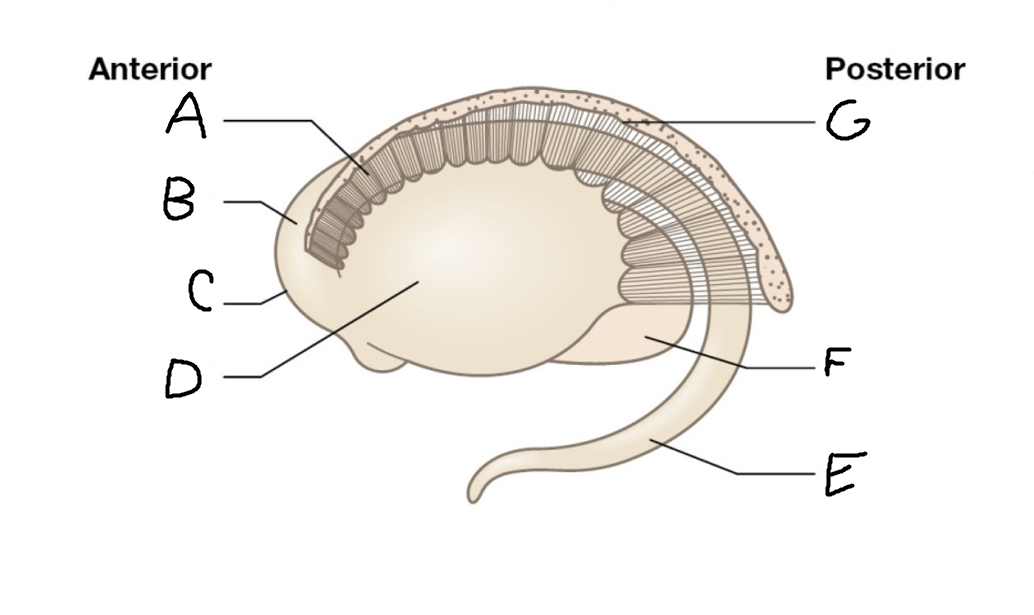

B

anterior horn of lateral ventricle

C

head of caudate nucleus

D

internal capsule (anterior limb)

E

putamen

F

globus pallidus

G

Thalamus

H

External capsule

I

internal capsule (posterior limb)

J

tail of caudate nucleus